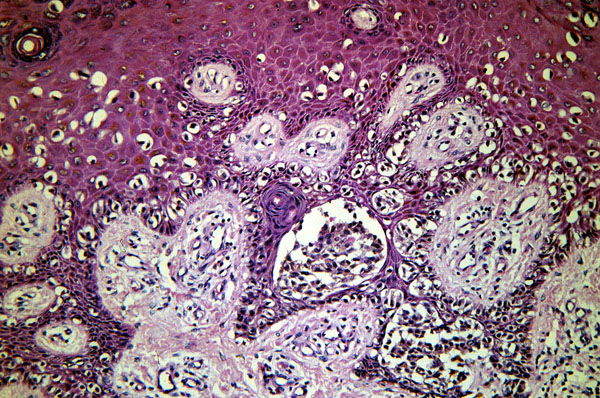

Radial growth phase melanoma, micro, center of the lesion, same irregular scatter of individual malignant melanocytic cells in the epidermis and papillary dermis as seen in the above slide.